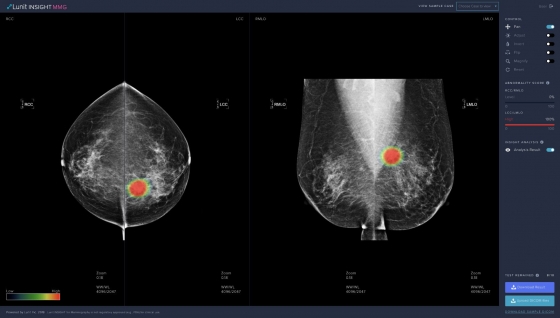

ÇÑÆí, º» ¿¬±¸¿¡ »ç¿ëµÈ AI ¡®·ç´Ö ÀλçÀÌÆ® MMG(Lunit INSIGHT MMG)¡¯¿¡ ´ëÇÑ ³ôÀº Á¤È®¼ºÀ» ÀÔÁõÇÏ´Â ³í¹®Àº Áö³´Þ ¹Ì±¹ÀÇÇÐÇùȸ Á¾¾çÇмúÁö(JAMA Oncology)¿¡µµ °ÔÀçµÆ´Ù.

ÇöÀç ·ç´Ö ÀλçÀÌÆ® MMG´Â ½Ä¾àó Çã°¡ ¹× À¯·´ CE ÀÎÁõÀ» ȹµæÇØ ±¹³»¿Ü ÇコÄÉ¾î ±â°ü µî¿¡¼ »ç¿ëµÇ°í ÀÖ´Ù.